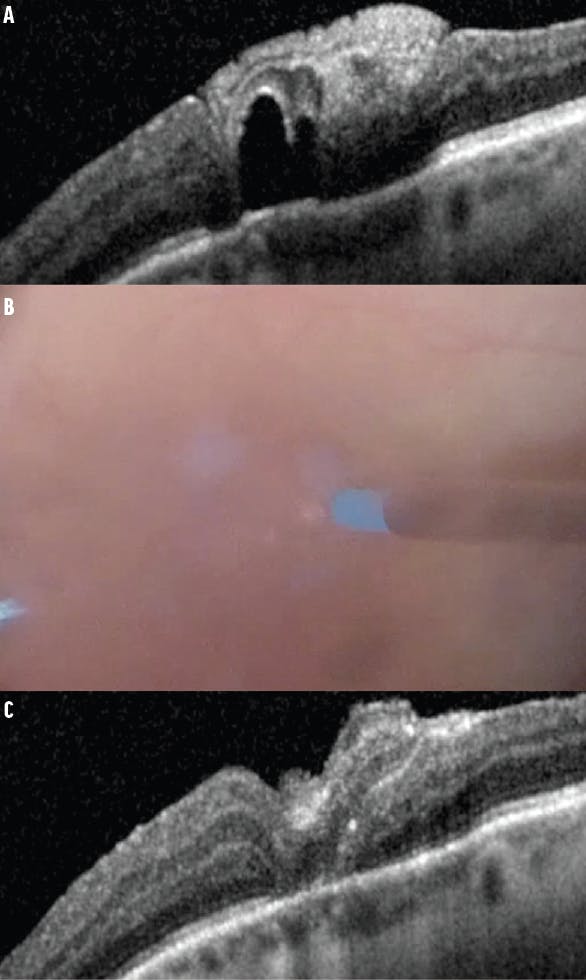

Before and at the time of PFCL removal, it is essential to recognize slight graft displacement (as opposed to dislocation), occurring in approximately 10% of ART procedures.3 If an eccentrically displaced graft is noted before PFCL removal, an adjustment can be performed. Although ILM forceps can be used for this, the Finesse Flex Loop (Alcon) may serve as a useful tool to gently manipulate the ART in the direction of the eccentric displacement under PFCL (Figure 1). After the adjustment, PFCL-air exchange with subsequent intraocular gas exchange is appropriate.

Figure 1. OCT demonstrates an eccentric ART with a nasal opening (A). Intraoperative photographs document before (B) and after (C) an adjustment of the ART. The post-adjustment OCT demonstrates good closure (D).